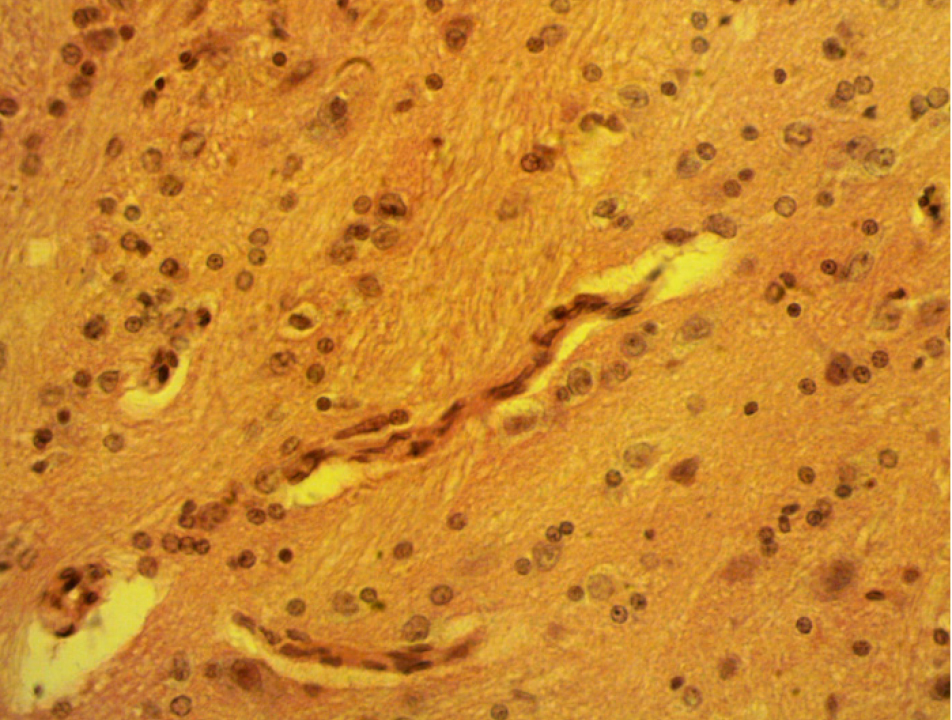

В то же время ремоделирование ангиоархитектоники и структурной организации мозжечка после ЧМТ в высокогорье отличается от данных опытов в низкогорье по степени выраженности и направленности. Так, после ЧМТ в низкогорье отмечается генерализованный спазм мелких артериальных ветвей и артериол, что вызывает ишемию мозжечка (рис. 1). Тогда как в высокогорье наблюдается венозная гиперемия и повышенная капилляризация мозжечка (рис. 2).

После ЧМТ в высокогорье чаще, чем в низкогорье, встречаются кровоизлияния на месте приложения травмы, по ходу кровеносных сосудов, залегающих в бороздах между дольками, в веществе мозжечка и даже полости IV желудочка. Наряду с паравазальными, наблюдаются интравазальные изменения в виде сепарации крови, тромбообразования, высокого капиллярного гематокрита.

Со стороны сосудистой стенки встречаются нарушение целостности эндотелия, отечность медии с образованием лакун и щелей, а также появление причудливого очертания. В определенной мере изменения капиллярного гематокрита можно интерпретировать как выброс крови из депо в кровеносные сосуды [25, 26], а формирование внутрисосудистых тромбов с гиперкоагуляционной направленностью крови в первые дни пребывания в высокогорье [25]. Особняком стоит вопрос о механизме комбинации высокого капиллярного гематокрита и плотности капиллярной сети. ЧМТ сопровождается повышением в СМЖ фактора роста эндотелия сосудов (VEGF) и эритропоэтина [27]. Отсюда можно предположить, что VEGF ведет к гиперкапилляризации, а эритропоэтин – росту капиллярного гематокрита, тем более что ЧМТ моделировалась в условиях высокогорной гипоксической гипоксии, а HIF был впервые обнаружен как регулятор транскрипции эритропоэтина, который представляет собой белок-регулятор кроветворения, экспрессирующий преимущественно в почках и, в меньшей степени, в печени [28, 29]. Обращает на себя внимание более усиленная капилляризация ганглионарного слоя коры мозжечка, чем молекулярного и гранулярного, что может быть обусловлено несколькими причинами. Первое – гиперфункцией грушевидных нейронов, как главных нервных клеток коры мозжечка, требующей дополнительного обеспечения кислородом и нутриентами. Второе – грушевидные нейроны и кровеносные сосуды, в том числе капилляры сосудистого сплетения головного мозга (ССГМ) вырабатывают морфоген Sonichedgehog (Shh), который влияет на нейро- и ангиогенез [30, 31]. Иначе говоря, в своем развитии и функционировании грушевидные нейроны коры мозжечка и ССГМ взаимосвязаны. Надо полагать, что в экспериментальных условиях эта взаимозависимость обостряется.